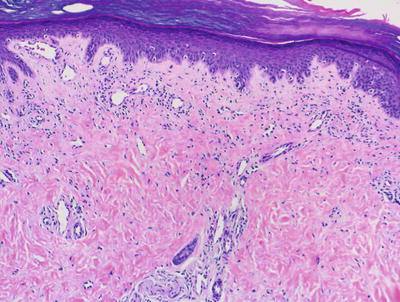

Lichen planus occurring in children has similar histologic features to the same disease in adults. The stratum corneum is hyperkeratotic without acanthosis. The epidermis is acanthotic with hypergranulosis (Fig. 4.2). The rete ridges demonstrate a saw-toothed alteration in appearance. The basal layer is disrupted and in some places obscured by a dense, band-like infiltrate of lymphocytes along the dermal epidermal junction (Fig. 4.3). Dying keratinocytes are present either focally or extensively, resulting in separation of the epidermis from the dermis. In some cases, this may present with clinically apparent bullae (bullous lichen planus) [2]. In older lesions, especially in patients with darker skin tones, post-inflammatory pigment incontinence is detected in the presence of papillary dermal melanophages (lichen planus pigmentosus in its most extensive form). The inflammatory infiltrate consists of lymphocytes and histiocytes. Eosinophils and plasma cells are not common. The infiltrate is restricted to the papillary dermis, and does not ordinarily extend into the reticular dermis [3–5].

Fig. 4.3

In some cases of lichen planus, the epidermis appear papillomatous and hypergranulotic. Scattered dying keratinocytes are seen along with a dense band-like infiltrate and focal exocytosis of lymphocytes into the epidermis